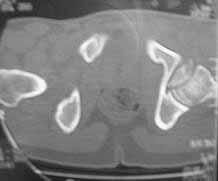

Male 22 yrs of age, RTA, front seat passenger in a truck. Sustained grade IIIB fracture of Tibia, and a Posterior dislocation of the Ipsilateral Left Hip.

Emergent closed reduction performed, and Tibial wound debrided. Next day Exfix applied and fibula plated. Initially femoral head fracture was not appreciated and it was thought that this is a posterior wall fracture. Presently two weeks down the line, Tibial wound is better but not completely healthy. and plastics want to wait for another five days, before they flap it. I enclose radiographs, Judet view, Ct scans in this and following mails.

Based on the selected images that you shared with us, I would not leave it as is. The fragment is significant in terms of its size and location and displacement.